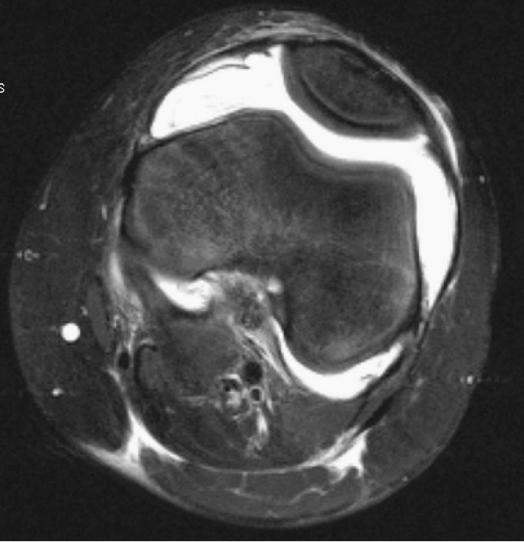

国外通过核磁共振检查,发现只被诊断为膝关节骨性关节炎的患者60%有滑膜炎,66%有关节积液。如果再做增强核磁,中到重度的骨关节炎患者95%有不同程度的滑膜炎,并且与疾病的严重程度呈比例。所以,很多急性或慢性的骨关节炎患者可能存在着滑膜炎,只是体检没有发现而已。现在B超检查既方便又快捷,如果怀疑滑膜炎可以选择,比体检要精确。